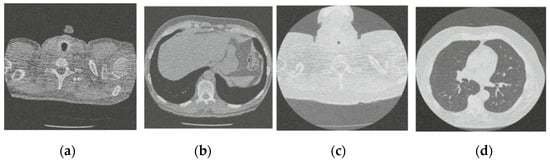

Figure 11.

Results of the proposed CT image denoising method; (a) Denoised CT1 image; (b) Denoised CT2 image; (c) Denoised CT3 image; (d) Denoised CT4 image.

For effective comparison to other systems available out there, this system has been pitted against seven of the most robust and widely used denoising techniques out there, i.e., Figure 4, Figure 5, Figure 6, Figure 7, Figure 8, Figure 9, Figure 10 and Figure 11. All the denoising frameworks performed reasonably well, with similar levels of denoising in their outputs, within a certain margin of error and variations. The result from these techniques for four CT images is displayed in Figure 4, Figure 5, Figure 6, Figure 7, Figure 8, Figure 9, Figure 10 and Figure 11. The CT image manipulation gave rise to redundant overcorrection, cumulating in distortion of the black borders and the introduction of fuzziness. Only two CT images from the rivaling systems have managed to preserve the blackness of the outer borders in the CT images. The result from [45] in Figure 9c is the least clear, with distortion visible to the unaided observer. A similar problem is observed in Figure 4a,c, where the system overcorrects, introducing more distortion instead of improving clarity. Figure 10d comes closest to the original, though the proposed framework is superior, as illustrated in the next section. From Figure 11a–d, it is very clear that the proposed algorithm gives better outcomes in comparison to existing methods in terms of clinical features, such as edges, textures, contrasts, and brightness.